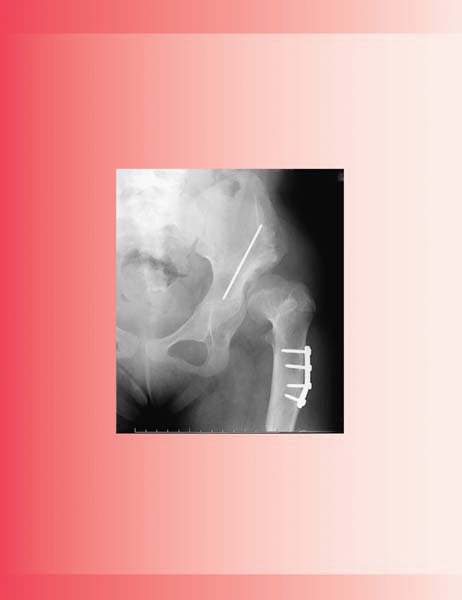

▪ FIGURE 21-1 (A,B)

The parents of this 16-month-old girl were concerned that she was not walking right. She has significant lordosis and a waddling gait. Dislocated hips were discovered incidentally on a urethrogram. An AP radiograph of the pelvis demonstrates bilateral dislocated hips (C). |